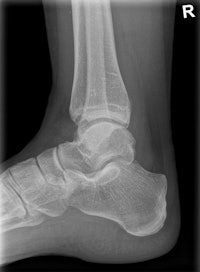

Clinical image of an x-ray examination of the ankle joint. Copyright: Radiology Department, University Hospital Erlangen, Germany. Image courtesy of Siemens.The machine can record static, dynamic, and real-time 3D sequences, and the full range of its potential applications is still to be explored. But there are clinical applications in which it already appears to have advantages over CT, notably in investigations of upper limb fractures in obese patients and weight-bearing lower-limb bone examinations of diabetics, he added.

Tomosynthesis image of an ankle taken with Shimadzu's RADspeed Pro digital radiography system.The emphasis of Philips' researchers has been on developing technologies for improving diagnostic quality while eliminating inefficiencies when using mobile digital radiography systems at the patient's bedside. The new SkyFlow scatter correction algorithm reduces the effect of scattered radiation for nongrid bedside chest exams, allowing the operator to obtain DR images with grid-like contrast, but avoiding the time and effort involved in attaching and detaching a grid.